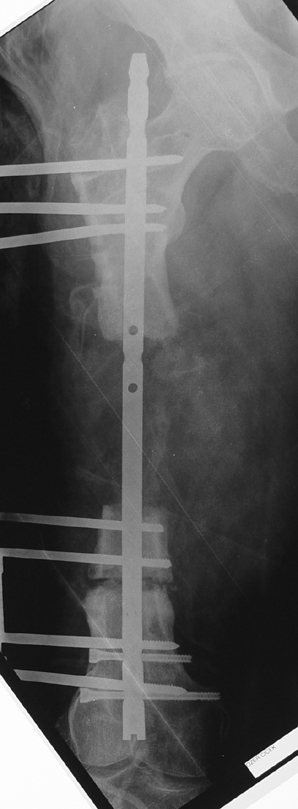

The duration of external fixation (external fixation index) depends on the amount of distraction required, and the extremity is prone to complications during this period. After the distraction phase is completed, the external fixator remains in place during the consolidation phase, which lasts twice as long as the distraction phase; but this period is hardly tolerated. If the external fixator is removed before sufficient consolidation is achieved, fractures, deformity and shortness will be the result. In our department, ‘lenghthening over nail’ method is used in order to decrease the external fixation index and increase patient comfort and activity level. In this method, the intramedullary nail is statically locked after the completion of the distraction phase, and external fixator is removed. The extremity is stabilized by the intramedullary nail during consolidation phase. In this way, complications due to long external fixation index or early removal of the external fixator are avoided.